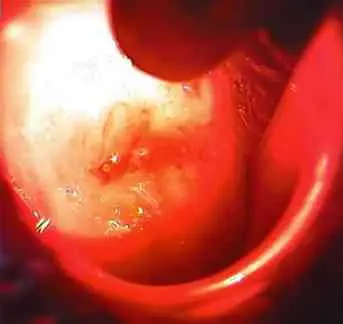

Диагноз: цервикальная интраэпилиальная неоплазия II-III степени

cin II-III степени

Сеанс ФДТ

Через 30 дней диагностировано выздоровление

Эрозия шейки матки, цитологический диагноз дисплазия CIN 1,2,3... Думаю, всем понятно, что ядерную бомбу в своем организме под названием предрак никому носить не хочется. А что делать? Прижигать. Как? Самым лучшим способом. А это на сегодняшний день фотодинамическая терапия. Давайте посмотрим фото!

Флюорисцентная диагностика через 2 часа после введения ревиксана

Здоровая шейка матки после сеанса фотодинамической терапии